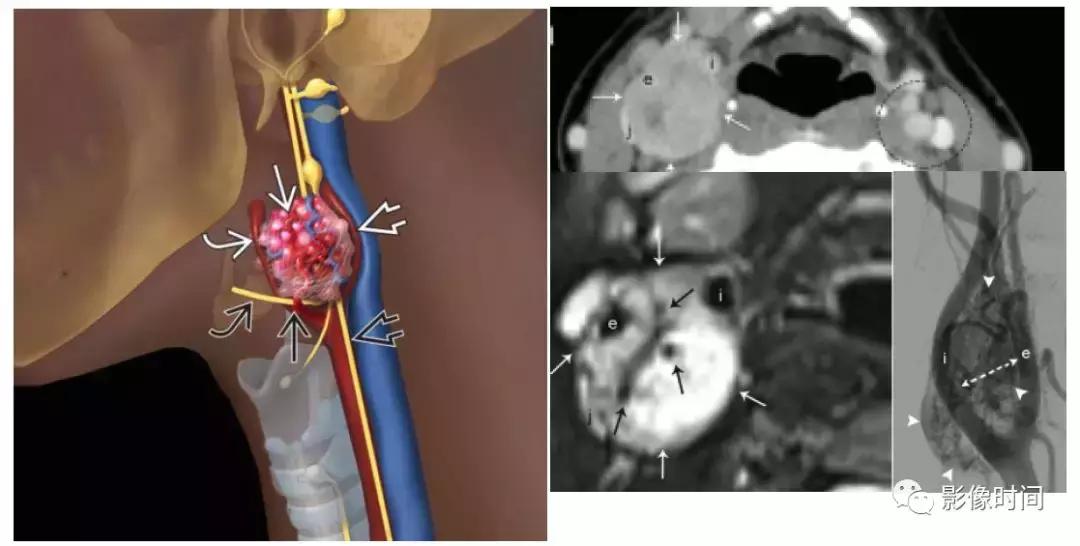

(1).颈动脉体瘤:约占颈部副节瘤的 60%,45-60 岁多见,无明显性别差异。多位于颈总动脉分叉处内侧,往往生长缓慢和无痛,由于病灶靠近 10-12 颅神经,因此患者可以出现吞咽困难、声音嘶哑等。

模式图显示颈动脉体瘤富含血管,并导致颈内动脉及颈外动脉距离增宽,包绕颅神经。增强 CT 显示右侧动脉间隙中心的边界清晰肿块,导致颈内动脉 (i) 和颈外动脉 (e) 分离。颈内静脉向外后移位(j)。左颈动脉间隙 (虚线圆) 显示颈动脉与颈内静脉的正常关系。T2WI 显示边界清晰的信号肿块 (白色箭头),多个内部流动信号 (黑色箭头)。DSA 显示颈动脉分叉处有富血管团块 (箭头)。